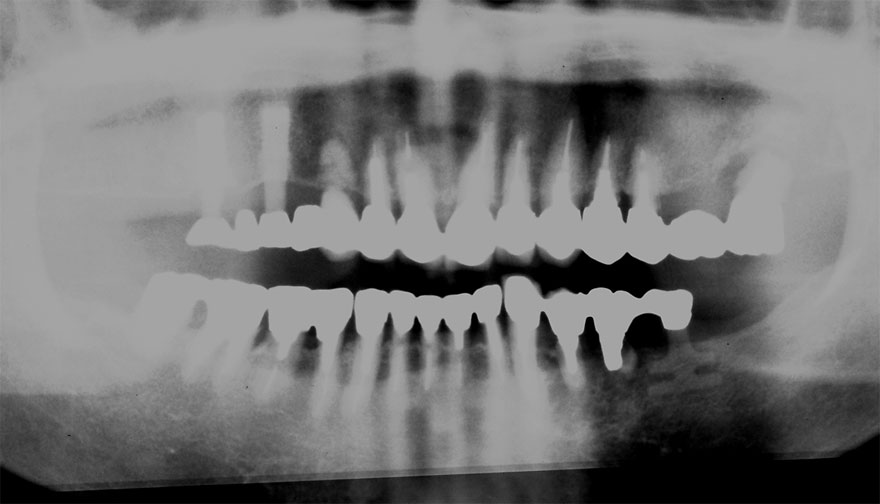

開始年齢 40代

初診時 40歳 女性 平均歯槽骨喪失量:3.14mm

32年後 72歳

平均歯槽骨喪失量:3.22mm

32年間喪失量:-0.08mm

年間喪失速度:-0.002mm

(ケア頻度:1.86ヵ月ごと)